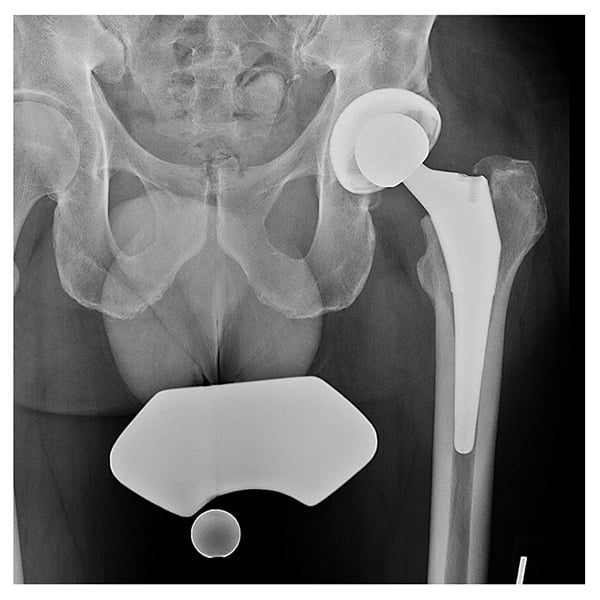

On examination, the patient was found to have persistent drainage and cutaneous pustules around his anterior incision and 2 draining sinuses. He had a body mass index of 28.5 and was febrile. Range of motion included 90° of flexion and 30° of external rotation, limited by pain. Due to his components being well fixed (Fig. 1), the patient agreed to undergo an extensile posterior approach to the hip.

Figure 1: Preoperative radiograph demonstrating a cementless THA with well-fixed components.